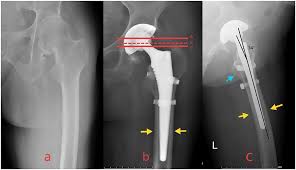

Successful precision hip replacement starts with a comprehensive pre-operative assessment. Patients undergo a complete medical evaluation, imaging studies, and physical examination. Advanced 3D planning software helps in mapping the hip joint, allowing the surgical team to select the appropriate implant size and positioning. Patients receive detailed guidance about the procedure, recovery expectations, and post-operative care. This meticulous planning ensures safety, accuracy, and confidence throughout the surgical process.

During precision hip replacement, minimally invasive techniques are used to access the hip joint with minimal disruption to surrounding tissues. The surgical team:

• Removes damaged cartilage and bone with precision

• Positions high-quality implants accurately

• Ensures proper joint alignment and leg length